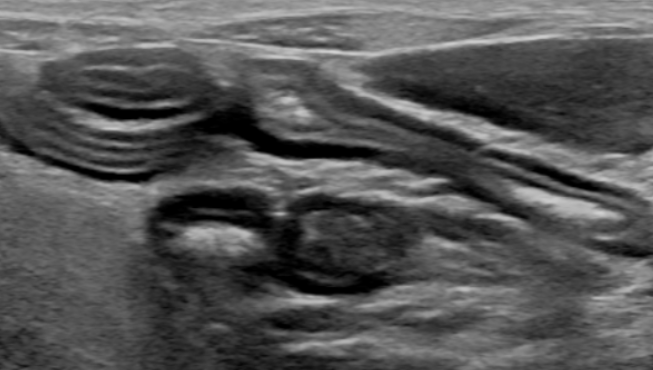

feline IBD(inflammatory bowel disease) cast ultrasonographic image sample

Well-demarcated thickening of the muscular layer with relatively preserved stratified wall structure.